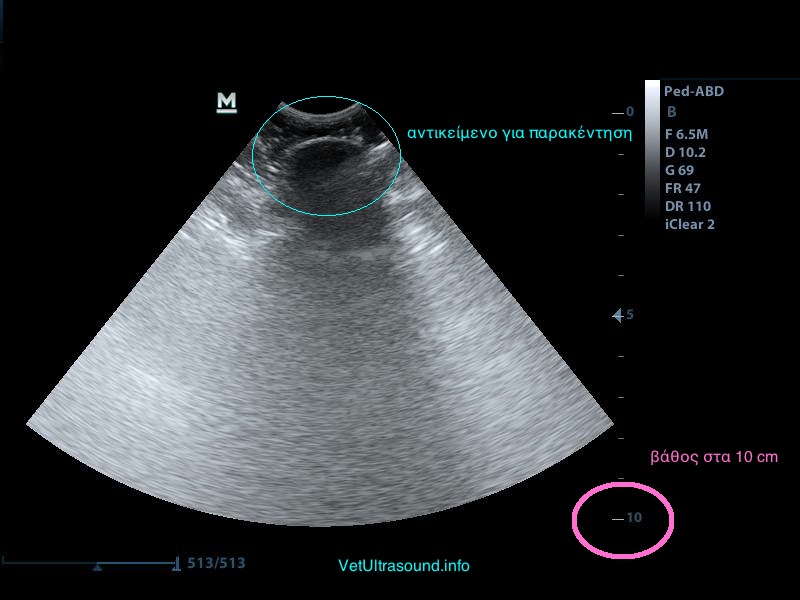

2) Το βάθος (depth), δηλαδή το να φέρουμε στην οθόνη του υπερήχου όσο το δυνατόν πιο κοντά το αντικείμενό μας, ώστε να καλύπτει σχεδόν τα 2/3 της οθόνης μας.

Μειώνουμε το βάθος ώστε να φέρουμε κοντά μας το αντικείμενο.